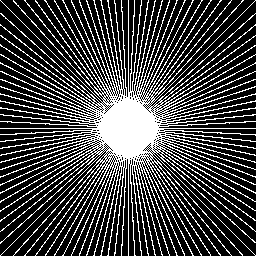

Figure 4: Radial k-space sampling pattern at 32%percent3232\% sampling ratio.

III-C Compressed Sensing Configuration

In order to evaluate the efficacy of the proposed CD-SFCRF framework at different sample rates, we first acquire MRI measurements at all k-space coefficients. Based on this fully-sampled set of k-space measurements, sparse sampling is then conducted using radial sampling patterns with different numbers of radial sampling lines to achieve a desired sampling rate. For example, Figure 4 shows a radial sampling pattern which corresponds to a sampling rate of 32%percent3232\% of the k-space. Different sampling rates are tested and evaluated in this study.